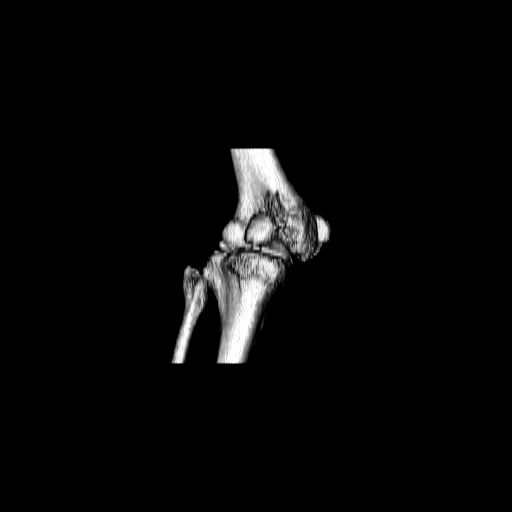

Качественные только исходные рентгенограммы (вышлю или завтра или в понедельник). Все последующие рентгенисследования были малоинформативны

(в т.ч. и последние снимки). КТ-исследование делалось 3 или 4 дня назад...

CT shows major bony fragments which are markedly rotated .With this amount of bony damage,you probably should attempt to get reasonably loooking knee with ORIF and thn if he needs a TKR due to pain a few years from now, then tleast you have something looking like a knee that you can replace rather than having to use revision knee for a primary TKR now. 4 weeks is not too long .what is the condition of soft tissues?

При внутрисуcтавных переломах трехмерные (3D) изображения, кроме красивого снимка, не дают полную информацию о состоянии отломков, самыми информативными являются корональные срезы на КТ и обычная длинная ренгенограмма конечности для сравнения оси конечности.